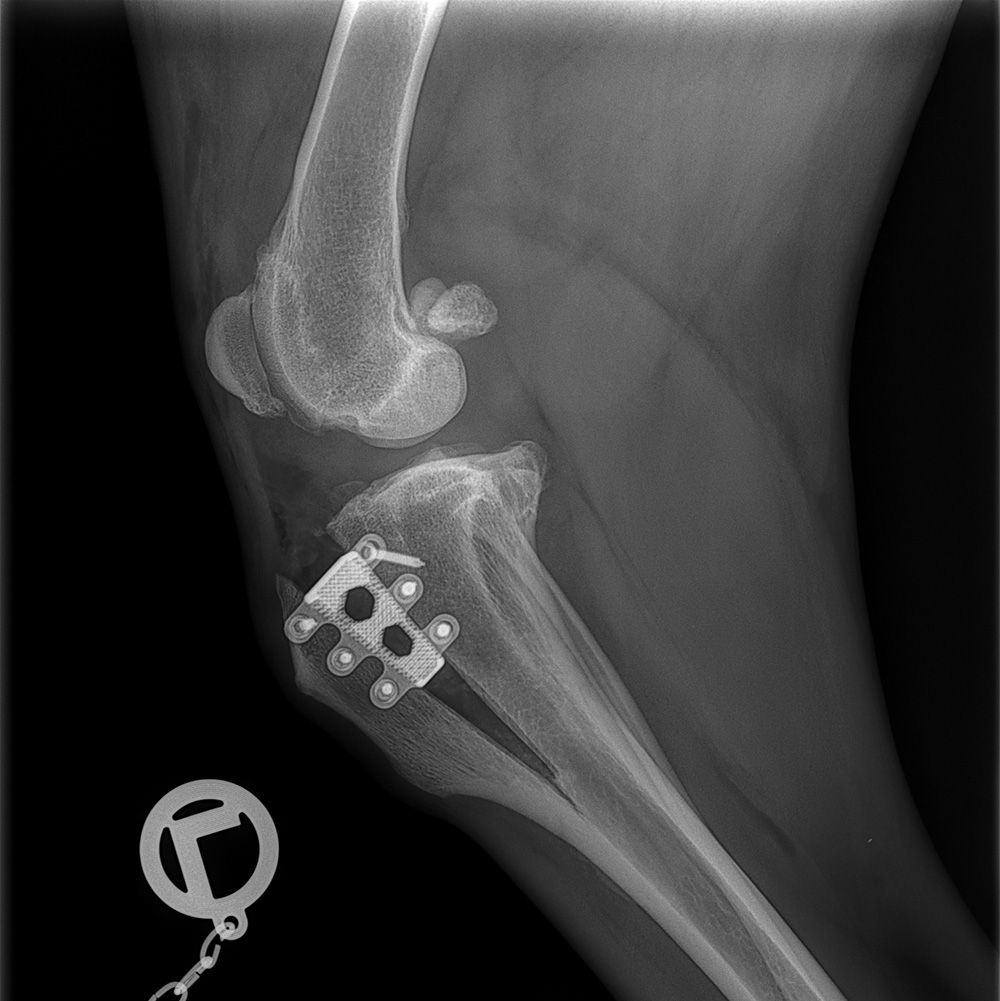

Die Behandlung des Kreuzbandrisses sollte somit auch die zugrundeliegende Ursache bekämpfen, d.h. in die Biomechanik des Kniegelenks eingreifen und nicht wie in der Humanmedizin im Bandersatz bestehen. Wir versorgen Kreuzbandrisse bei Hunden mittels Tibial Tuberosity Advancement (TTA)-OP. Dabei wird ein longitudinaler Knochenschnitt am Unterschenkel gesetzt und die Ansatzstelle des geraden Kniescheibenbandes mittels Titan-Implantat (Titan-Cage) nach vorne verlagert. Durch die TTA-Operation wird das Kreuzband nicht ersetzt, sondern durch eine veränderte Biomechanik des Kniegelenks unnötig gemacht. Das Kniegelenk kann nach dem postoperativen Heilungsprozess schmerzfrei belastet werden.

Neben dem TTA-Instrumentarium für normalgroße und große Hunde verfügen wir auch über das TTA-tiny-Instrumentarium für die Versorgung des Kreuzbandrisses bei kleinen Hunden und Toyrassen. Auch sind wir in der Lage die Kombination aus Kreuzbandriss und Patellaluxation mittels einer OP-Kombination (Rapid-Luxation) zu versorgen.